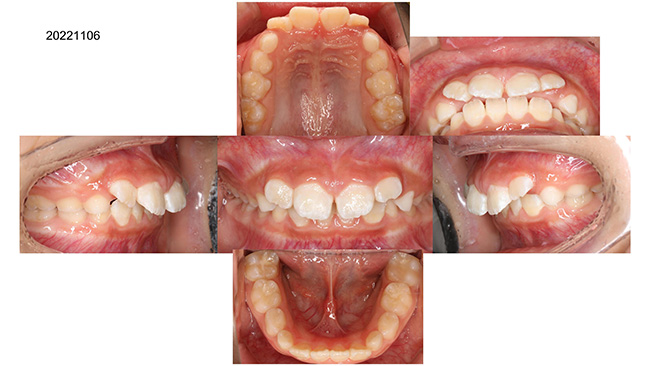

歯並びがガタガタの症例